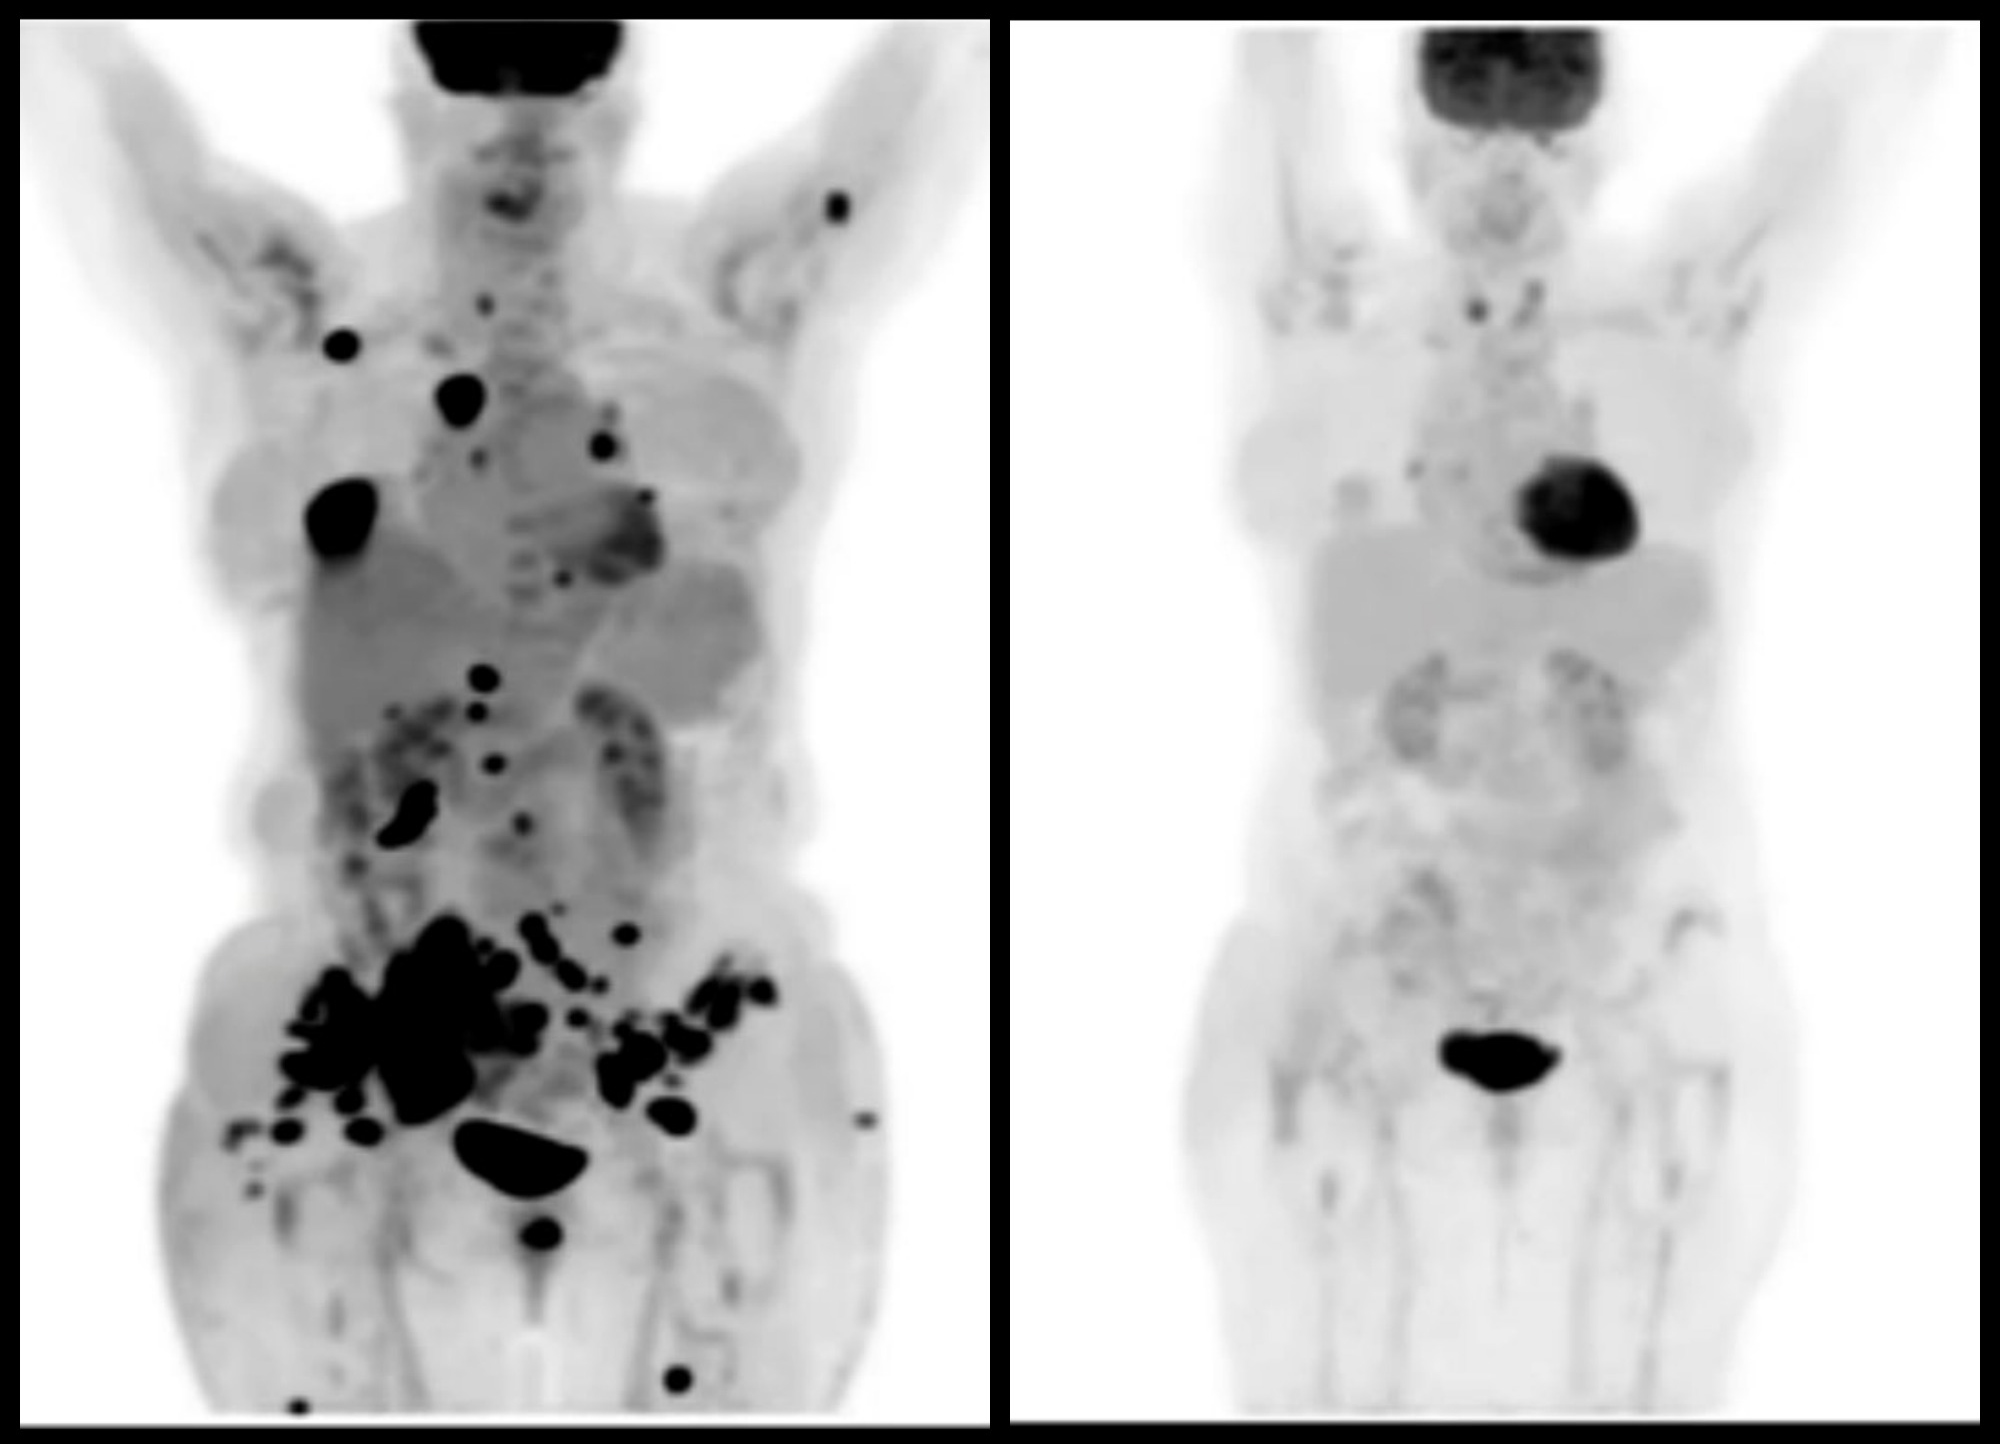

Predicting Response To Immunotherapy In Advanced Lung Cancer